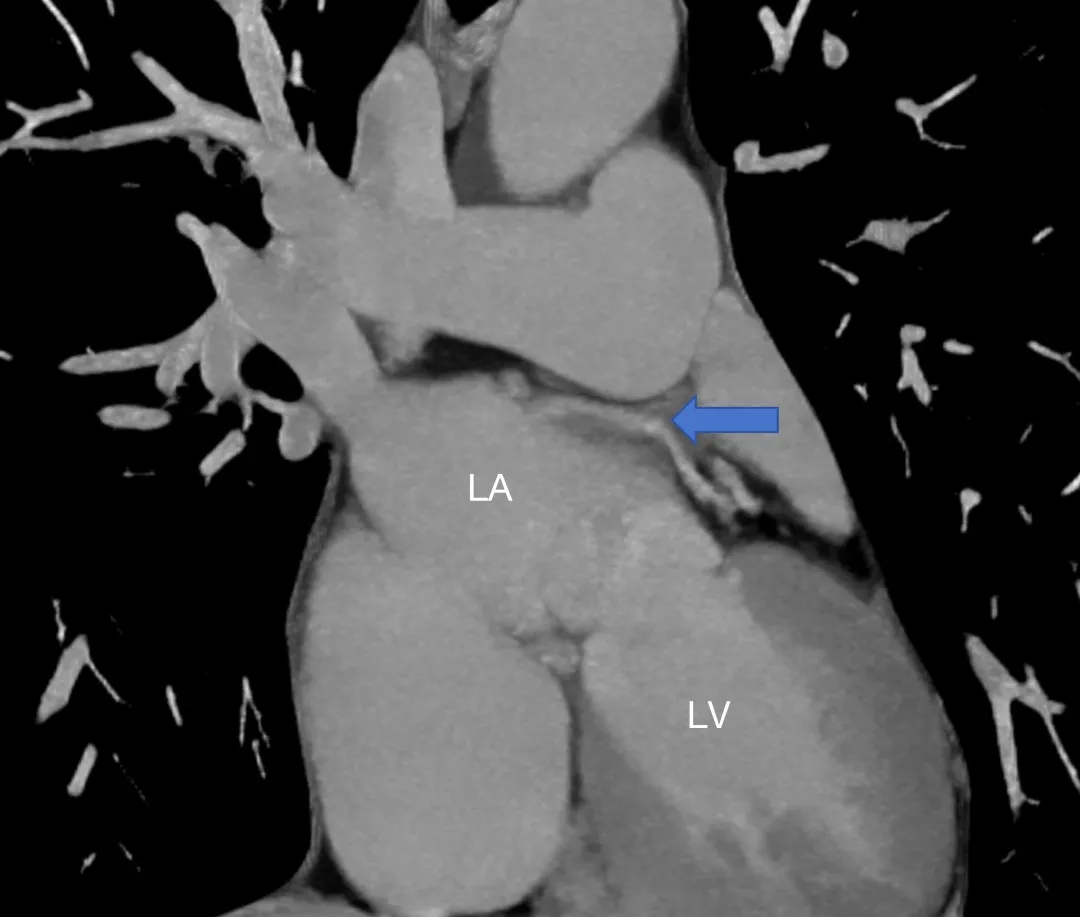

患者女性,27岁,因“卵圆孔未闭相关卒中”入院,拟行介入封堵术。术中MPA1导管跨越卵圆孔进入左心房后送入超滑导丝,发现导丝经由冠状静脉窦走行区回到右心房内,考虑导管进入异常通道,进一步造影可见一起自左心房前壁的冠状静脉分支血管沿房间隔水平横行走行,造影剂最终汇入冠状静脉窦,引流入右心房(图1&2,视频1&2)。该病情血液动力学类似冠状静脉无顶综合征/房间隔缺损,同期行右心导管测肺动脉平均压16mmHg,QP/QS=1.0,排除具有血液动力学意义的左向右分流。由于无法立刻明确单纯封堵PFO的收益与风险,遂终止手术先行完成心脏增强CT明确病变解剖情况,增强CT(图3&4)及重建结果(图5&6)与造影一致,可见一冠状静脉分支起自左心房并沿房间隔走行最终汇入冠状静脉窦。考虑到患者的临床症状可能与PFO以及该异常静脉均存在相关性,且尚不能明确单纯封堵PFO的收益以及同期封堵该静脉的风险,与患者充分沟通后暂时选择最优药物治疗并保持密切随访。

图4